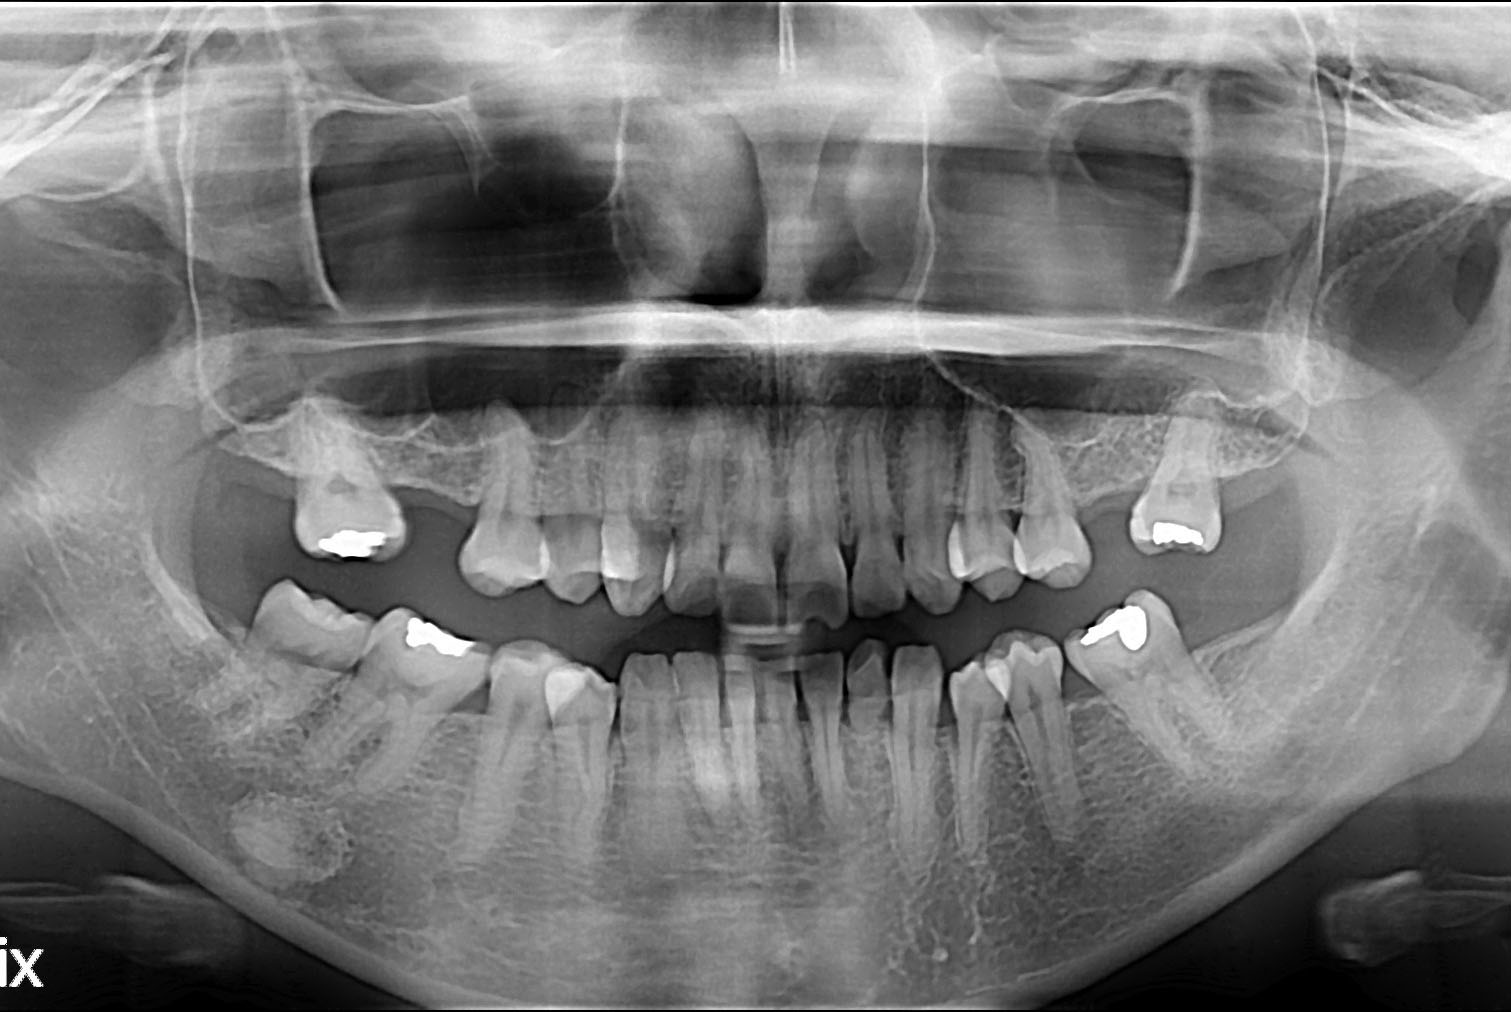

[임플란트] 임플란트

치료후 : 2019-08-01

세종치과는 많은 환자와 다양한 케이스를 바탕으로 항상 편안한 임플란트 수술을 제공하고자 노력하고,

오래동안 튼튼히 쓸 수 있는 임플란트 수술을 가장 큰 목표로 삼고 있습니다